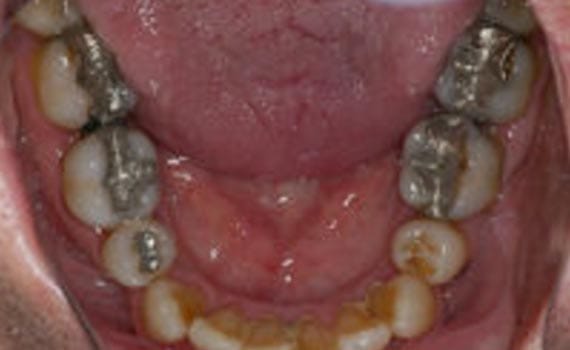

Surgical Templates: Implant Guide Basics 3D Imaging For Treatment Planning & Precise Implant Placement Virtual 3D Treatment Planning Derived CAD/CAM Drilling Guide Jawbone Refortification: Titanium Implants & Titanium Bridge #1 3D Treatment Planning For Full Mouth Teeth Replacement All Teeth Lost to Disease & Normal Wear & Tear Implant Placements In Healthiest Bone Creates Strongest Bite Jawbone Refortification: Titanium Implants & Titanium Bridge #2 Embedded Titanium Implant Frame For Severe Bone Loss Bone Too Thin For Implants Embeddable Implant Frame X-Ray Confirmation Of Embedded Frame Snap-On Cosmetic Denture Single Implant Molar Tooth Replacement Best Solution For Long Term Endurance (avoiding bridgework) Adding Bone for Simple One Tooth Replacement Avoiding Invasiveness of 3 Unit Bridge (no anchor teeth grinding) Before After Popular Choice for Molar Tooth Replacement Expected Extreme Bite Pressure Maintains Optimal Bone Health Avoiding Bone Loss That Commonly Occurs Under A 3 Unit Bridge Before After Molar Teeth Replacement via Guided Implant Surgery CT Scan Based Diagnostics Assures Rock Solid Placement – Balance Excessive Decay & Gum Disease Total Diseased Tissue Removal Surgical Guide Alignment New Molar Bite Health Tooth “Creation” for Congenitally Missing Canines Baby Teeth – Yes | Adult Secondaries – No Special Tissue Punch Eliminates Need For Gum Surgery Minimal Need For Grafting Products Precision Implant Alignment Check Final Abutment Prep Perfect Match For Mother Nature 3 Unit Bridge With Implant Anchors => Maximum Bite Strength Avoiding Failures Caused by Modifying Adjacent Teeth for Anchoring Maintain Bone – Adjacent Tooth Health Before After Get Started Today Request Appointment Meet the Doctor Watch Our Video